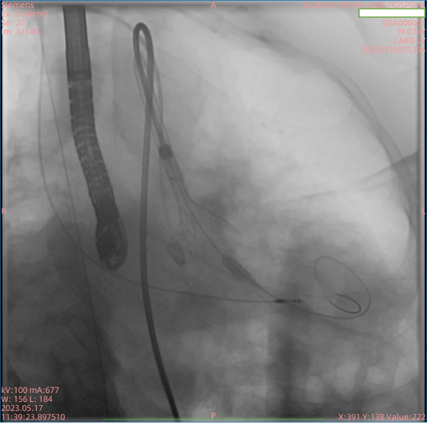

患者为74岁男性,因“反复胸闷1年余,加重1周”入住我院心内科病房。入院后完善心脏彩超,根据结果诊断为主动脉瓣重度狭窄。此次手术选用园区某生物医药公司自研的瓣膜,术前跨瓣压差测得68mmHg左右,术后即刻跨瓣压差小于5mmHg,手术效果较好。

本次TAVR手术所使用的瓣膜为园区某生物医药公司自主研发的经导管主动脉瓣系统,为二代可回收瓣膜,在提高TAVR手术安全性的同时,缩短术者学习曲线。我院期望将自身学科优势、技术优势与园区生物医药产业优势相结合,积极响应我国新医科“医工结合”、服务健康中国的理念,推动企业更快地将创新产品向临床转化。未来,医院将继续充分利用自贸区内生物医药产业的集群优势和政策利好,围绕新兴诊疗器械、创新药物、创新疗法及体外诊断试剂等方向,与企业共同产出一批有重大产业化价值的成果,促进相关学科的高质量发展。